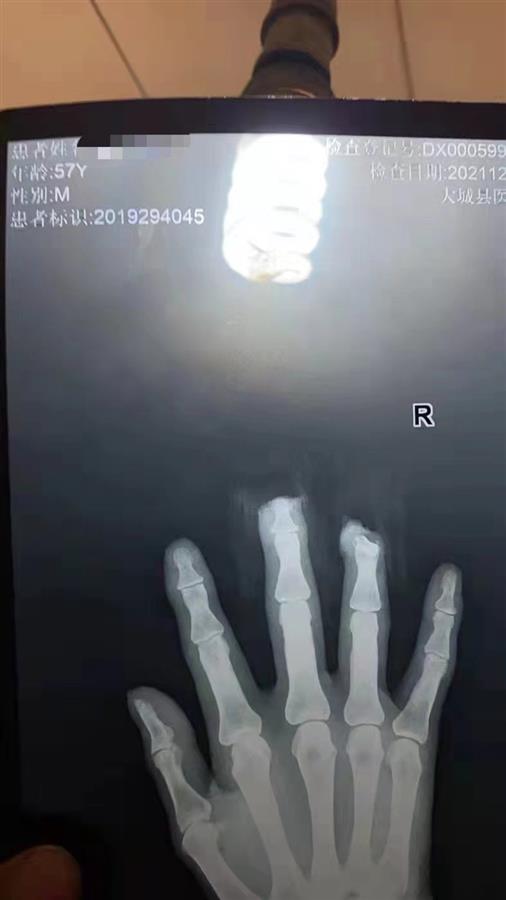

马驰父亲因受伤被截断两截手指

马驰说,30亩地的花生价值大约9万元,其中有部分花生已有人支付4万元定金买下,现在无法交货了。除了经济损失,他的母亲还在阻拦过程中,被摘花生的人推了一把导致手掌受伤。12月9日,他的父亲用机器在地里打花生时,就看到有人偷摘花生。忙着阻止村民偷摘,打花生的机器绞上了草,马驰的父亲回过头来处理机器时,被截断两节手指。